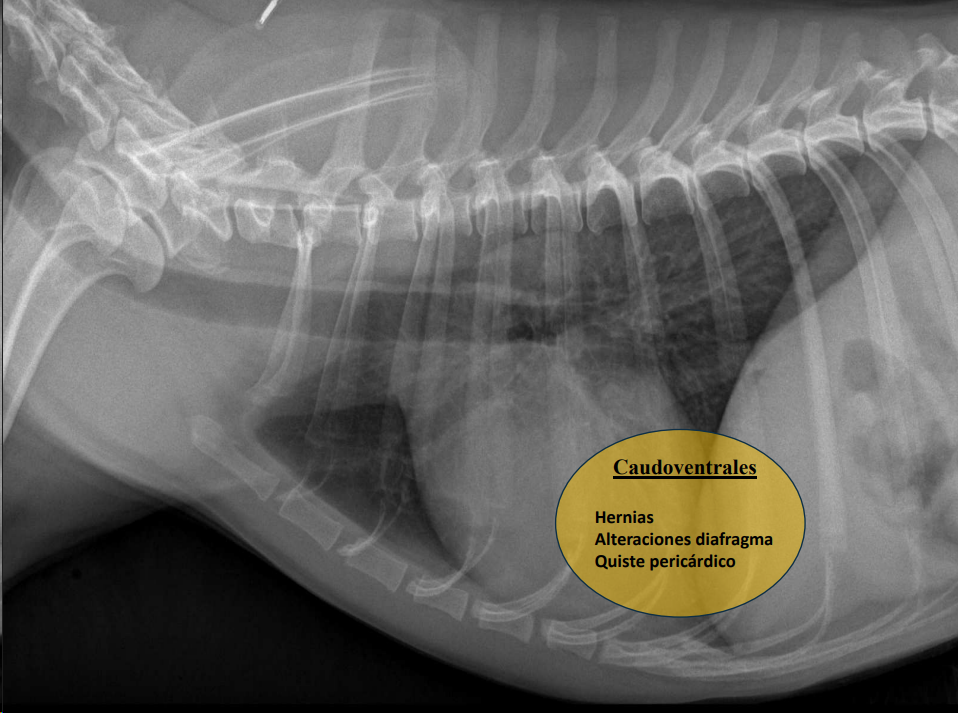

- Derrame mediastínico.

- Masas mediastínicas (craneodorsales, hilares, caudodorsales, caudoventrales, craneoventrales).

- Linfomas en gato, timomas en perros.

Caudodorsales: hernia paraesofágica, tumores neurogénicos, granulomas.

Craneoventrales: linfoma, timoma, tumor tiroideo, histiocitosis, lipoma, fibrosarcoma, linfoadenopatía esternal o craneal, absceso, aneurisma auricular.